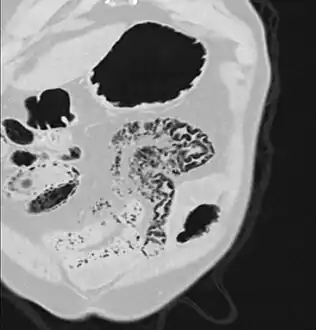

Pneumatosis intestinalis in the coronal computed tomography in lung window. It can be seen next to gas entrapment in the bowel wall and gas in the stomach wall and in numerous vessels, including the portal vein into the liver.

Pneumatosis intestinalis in computed tomography with intestinal ischemia. Lung window for better representation of the gas deposits in the intestinal walls.